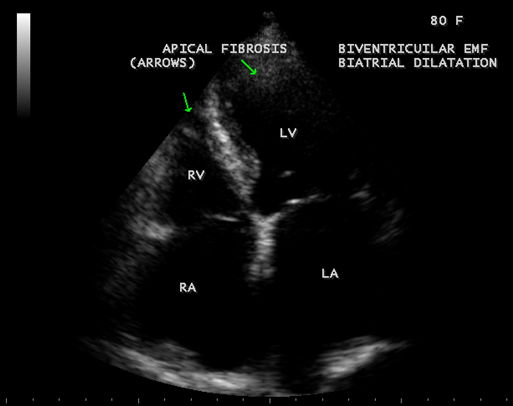

Figure 33: Endomyocardial fibrosis with biatrial enlargement in a 80-year old female suggesting biventricular EMF.